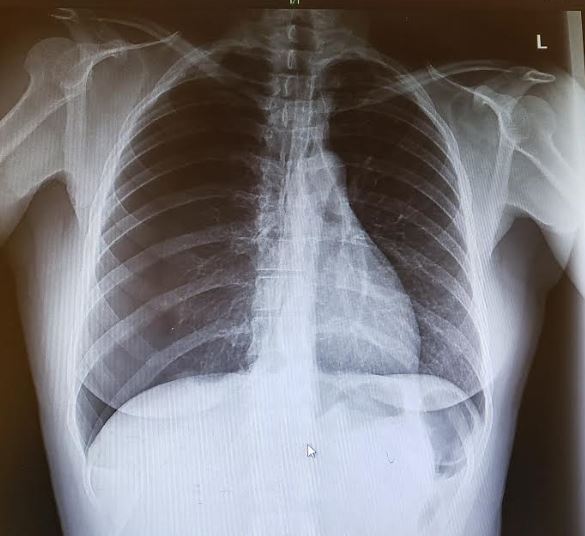

The presentation of this patient’s primary spontaneous pneumothorax was unique in that she had experienced the chest pain for 4 days, with no underlying medical condition and no smoking history. Although she was thin, she was 39 years old and female—characteristics that do not put spontaneous primary pneumothorax high on the differential diagnosis. The key to determining the diagnosis of spontaneous pneumothorax lies in the interpretation of chest radiographs. On this patient’s radiograph, the bronchovascular markings are seen clearly on the left and extend to the edge of the chest cavity. On the right side, there is a visible visceral pleural edge and no lung markings seen peripheral to the line. The radiograph shows a classic example of a right-sided pneumothorax.